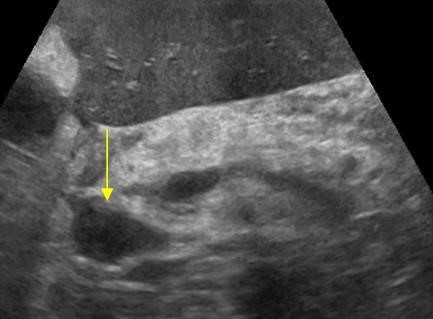

УЗИ диагностика кольцевидной поджелудочной железы: что важно знать